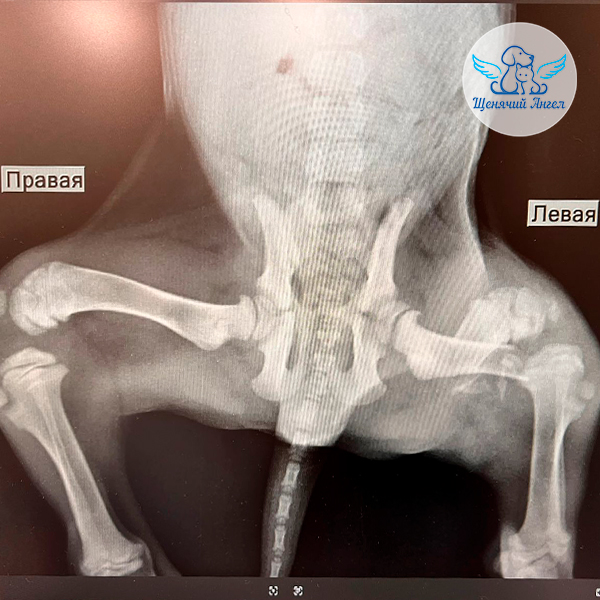

По результатам диагностики 🩻 у Амиго обнаружены травмы грудной и тазовой конечностей 🐾 (перелом костей предплечья и бедренной кости слева), а также возникло подозрение на диафрагмальную грыжу – опасное состояние, при котором органы брюшной полости могут смещаться в грудную полость и нарушать дыхание 😢.

После стабилизации состояния Амиго осмотрел врач-ортопед 👨🏻‍⚕️. Он подтвердил необходимость фиксации переломов, причём с учётом его возраста и состояния – сразу двух. Это даст малышу шанс быстрее встать на лапки и избежать осложнений 🙏🏻.

В клинике «Сколково Вет» хирург Горшков С.С. провёл Амиго остеосинтез костей предплечья и бедренной кости – установку металлических конструкций 🔩, которые фиксируют кости и позволяют им правильно срастаться.

В ближайшее время его осмотрит врач-реабилитолог, а через полтора месяца предстоит повторный приём хирурга и контрольный рентген, который покажет, как срастаются переломы ☝🏻.